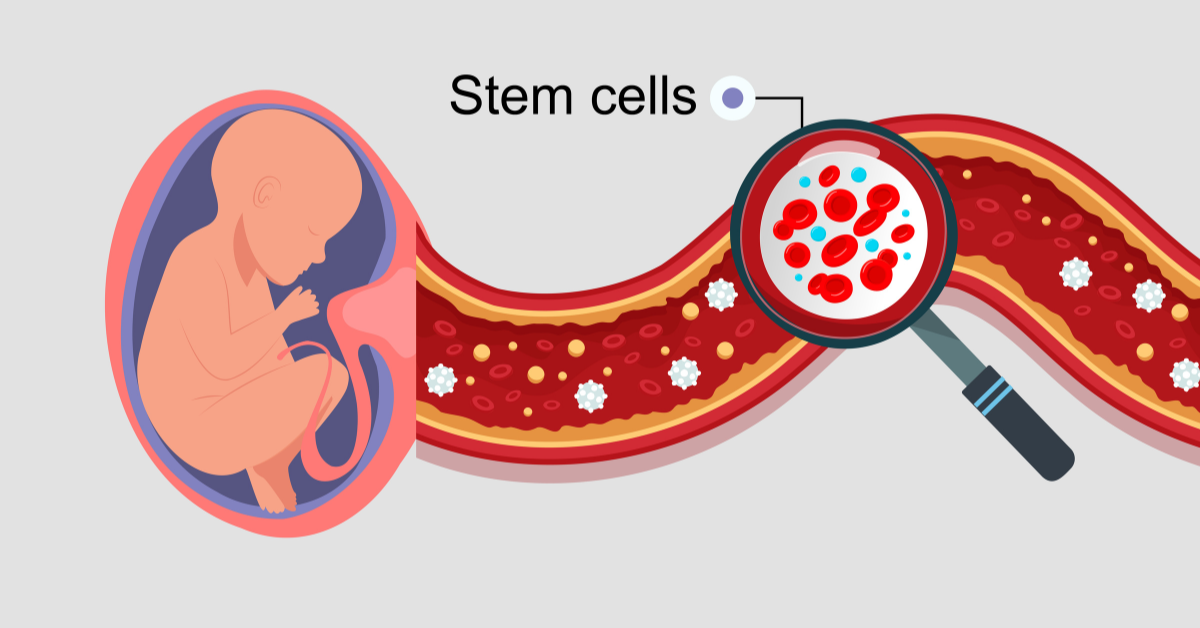

Cilj odloženog presecanja pupčane vrpce, kod zdravih porođaja u terminu, je da se omogući da deo krvi iz pupčanika uđe u novorođenče i poveća zapreminu krvi bebe i snabdevanje gvožđem.

Ovo ima brojne prednosti za bebu, ali smanjuje količinu krvi iz pupčanika koja se može uskladištiti za buduće zdravstvene potrebe bebe, bebine braće i sestara i bebine šire porodice.

Istraživanja su pokazala da u prvom minutu nakon zdravog porođaja beba dobija oko 80 odsto krvi koja će se vratiti iz pupčane vrpce, dok je u isto vreme količina krvi iz pupčane vrpce koja se može prikupiti za čuvanje u bankama krvi pupčanika prepolovljena.

Duže odlaganje pruža malu dodatnu korist za bebu, ali potpuno sprečava nakupljanje krvi iz pupčane vrpce. Medicinska udruženja akušera i ginekologa ne preporučuju odlaganje stezanja pupčane vrpce duže od jednog minuta.

Ako imate starije dete kome je potrebna krv iz pupčanika za terapiju, važno je da dobijete veliku količinu krvi iz pupčanika. Neke situacije u kojima se to može desiti su stariji brat ili sestra sa talasemijom ili stariji brat i sestra sa cerebralnom paralizom.